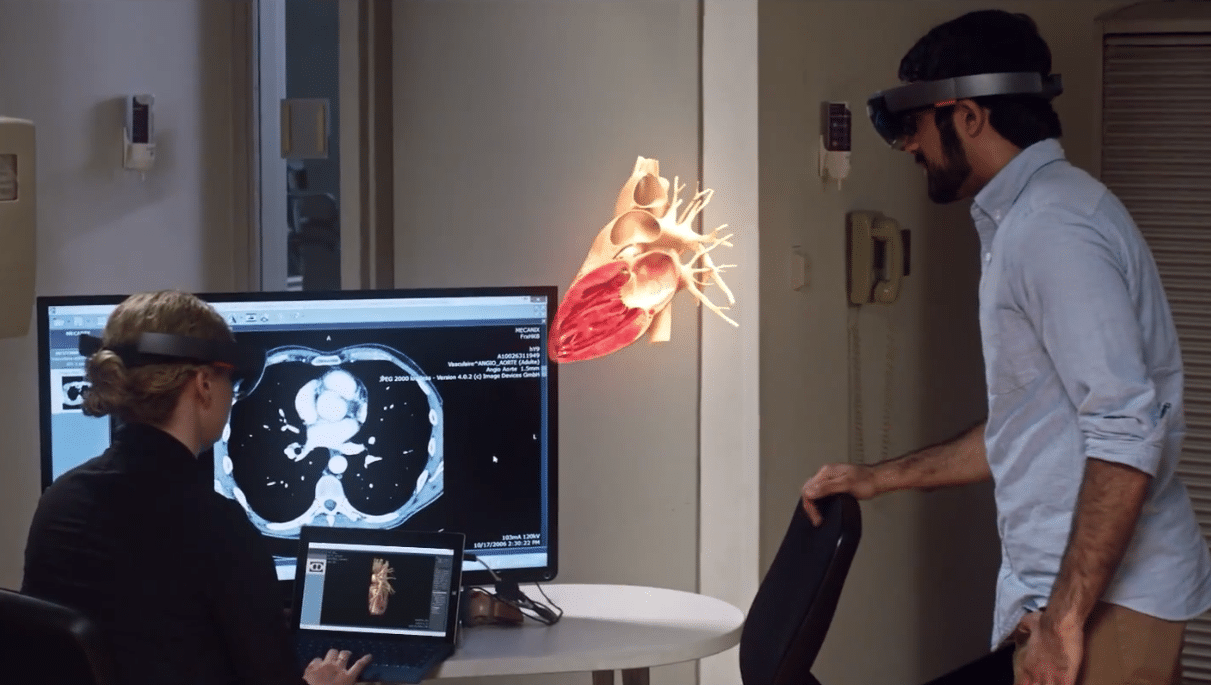

Dr. Richard Ljuhar: I think we all agree that radiologists (or more broadly speaking, human readers) will not be replaced by software algorithms. But I am convinced that physicians will embrace the benefits digital health offers. In a few years from now, there won’t be any image study seen by radiologists which has not been pre-analyzed by an AI algorithm first.

“In a few years from now, there won’t be any image study seen by radiologists which has not been pre-analyzed by an AI algorithm first.” (Credit: IB Lab)